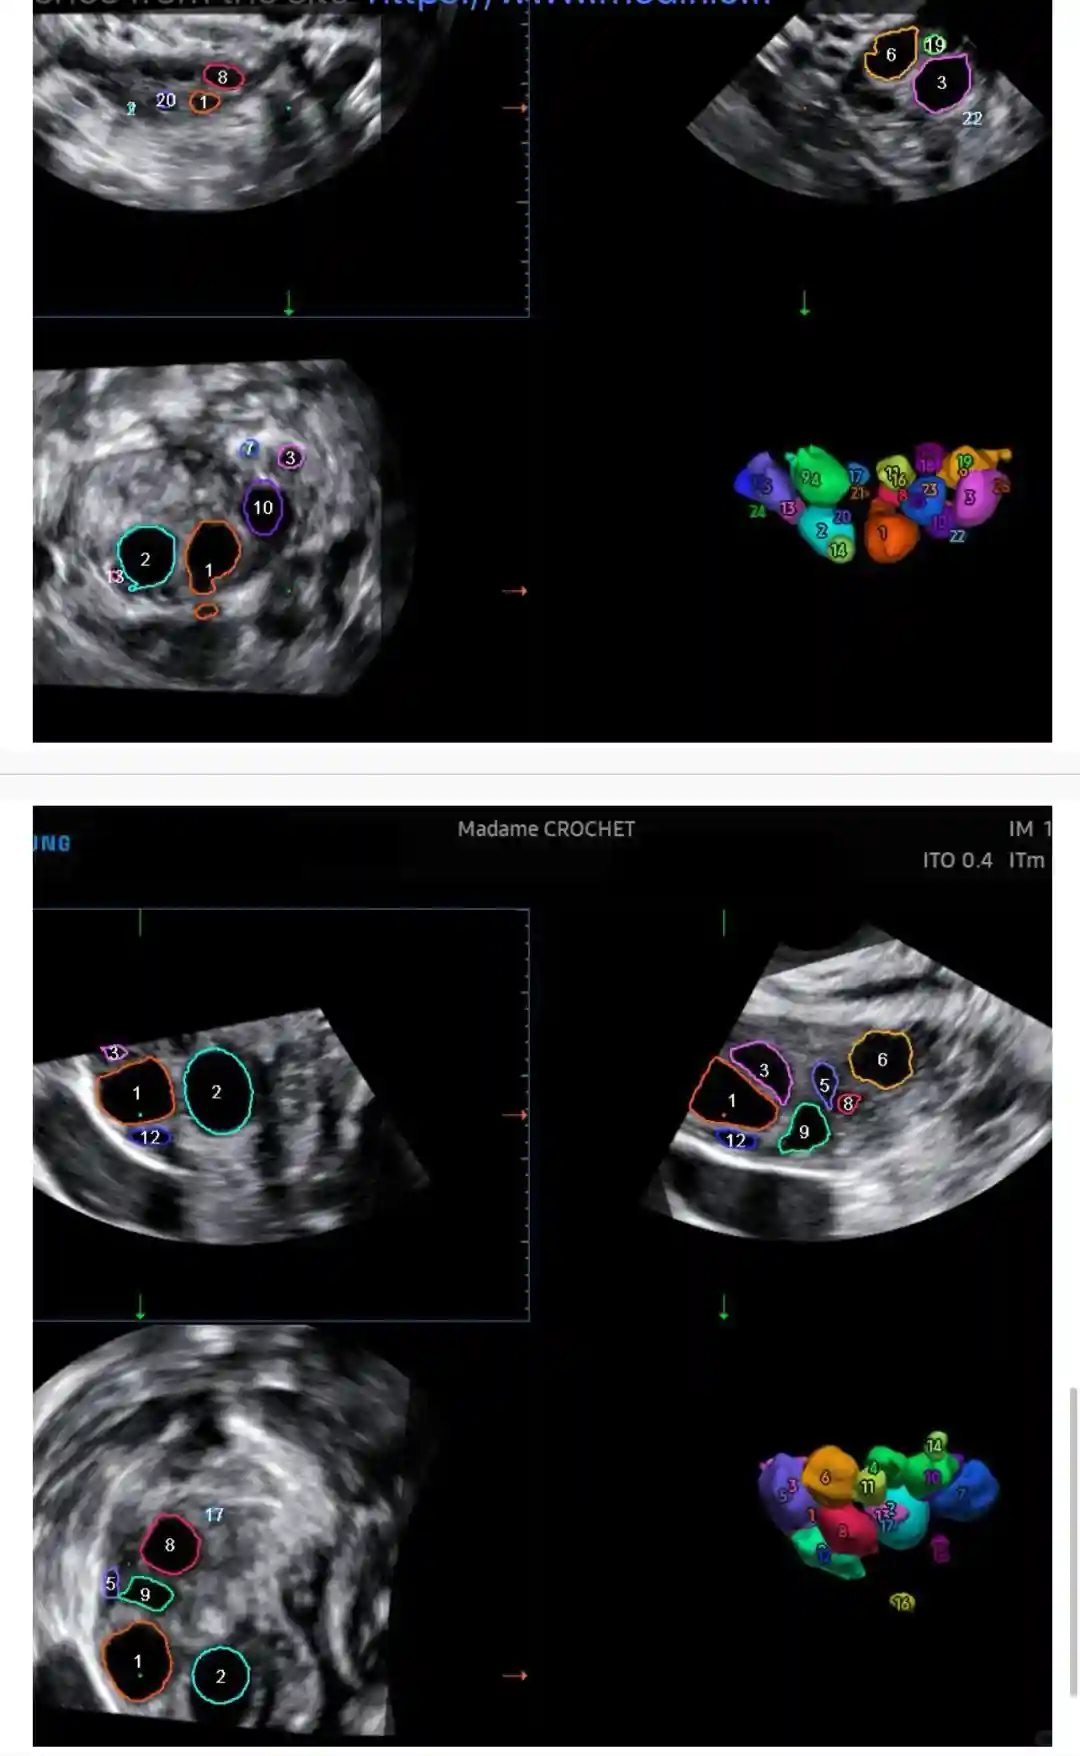

图123,打了4天Gonal-F验血及B超结果